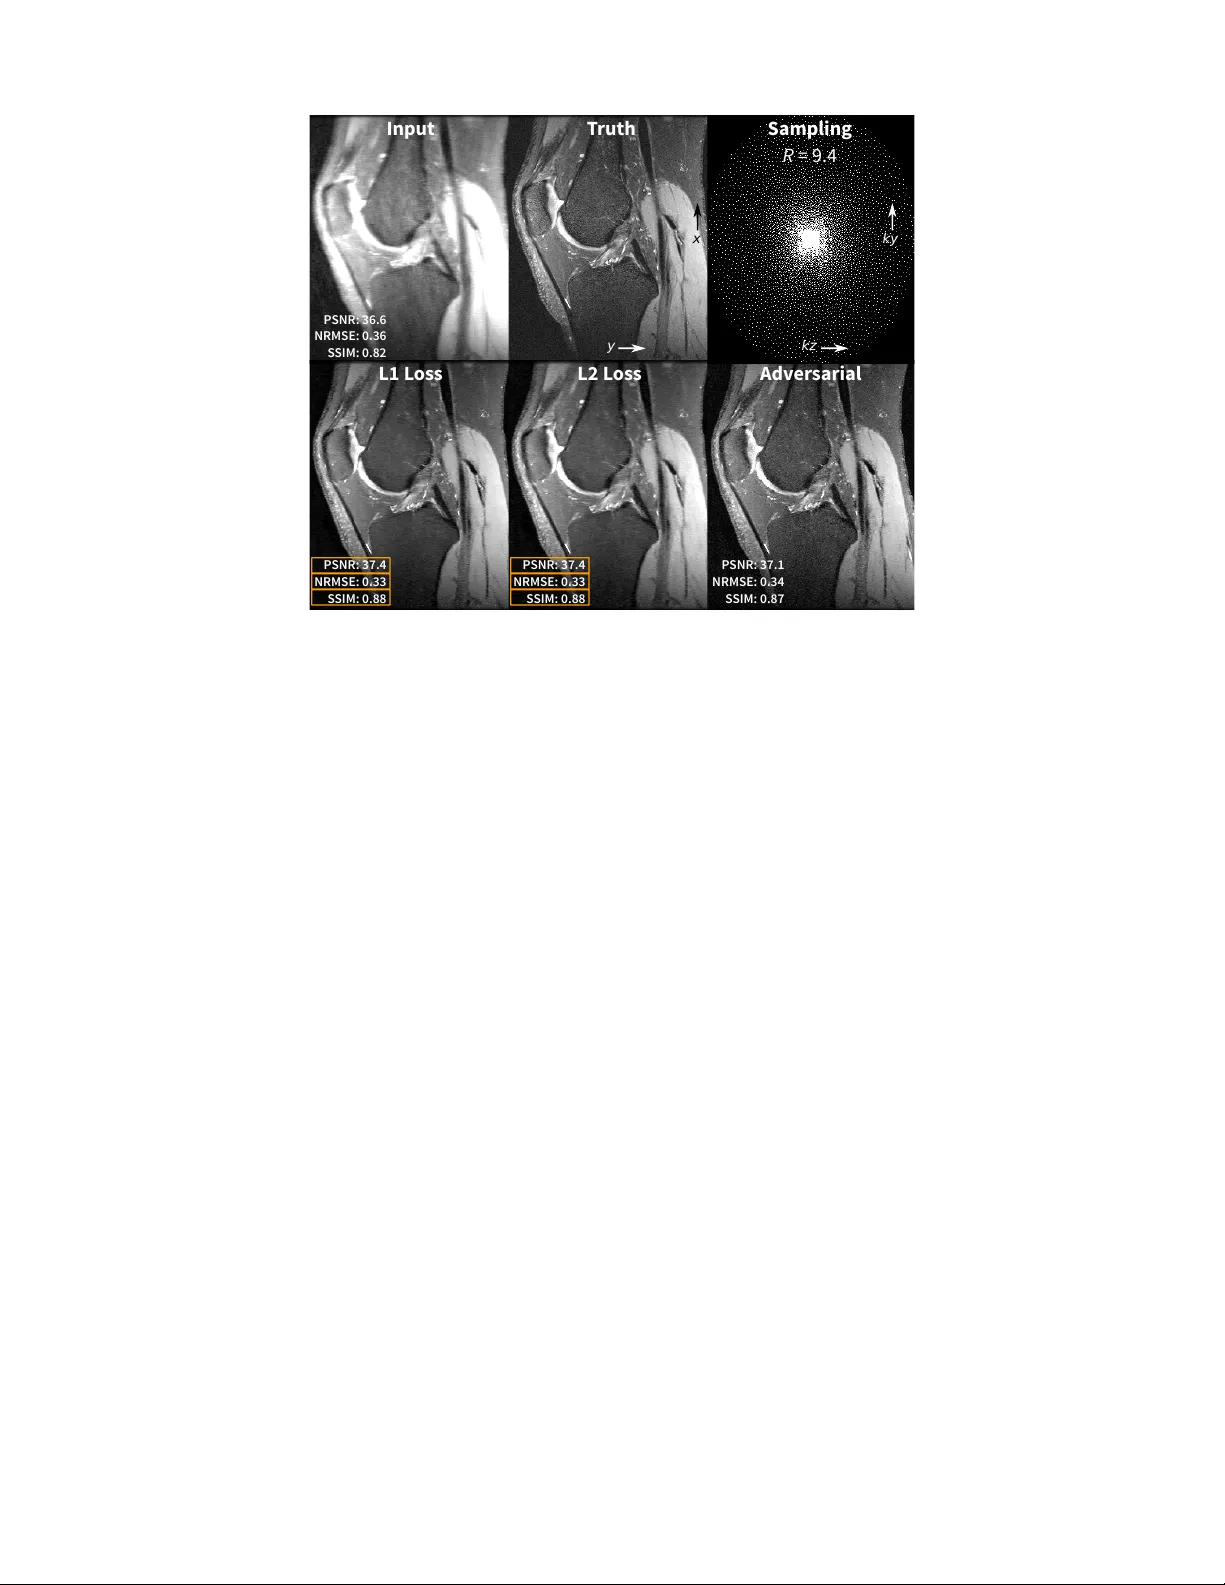

본 논문은 MRI 압축 센싱(Compressed Sensing, CS)의 임상 전이 과정에서 마주치는 주요 장애물—핸드‑크래프트 이미지 사전, 파라미터 민감도, 그리고 장시간 재구성—을 데이터‑드리븐 학습으로 해결하는 방법을 체계적으로 제시한다. 서론에서는 CS가 k‑space 샘플링을 크게 감소시켜 스캔 시간을 단축하고, 고해상도·고시간 해상도 영상을 가능하게 함을 강조한다. 특히 다차원(4D 흐름, 동적 대비 강화 등) MRI에서 10배 이상의 가속이 가능해 임상적 가치를 크게 높일 수 있음을 사례(A, B 그림)로 보여준다. 그러나 현재 상용 CS는 정규화 파라미터 λ 를 수동으로 조정해야 하며, λ 가 과도하면 세밀 구조가 소실되고, 부족하면 노이즈가 증폭되는 트레이드오프가 존재한다. 또한, 웨이블릿·TV·로우‑랭크 등 사전 정의된 변환이 텍스처 아티팩트를 유발하고, 반복 최적화(50~1000회)로 인해 재구성 시간이 수분에서 수시간까지 크게 변동한다는 점이 임상 적용을 저해한다. 이러한 문제를 해결하기 위해 저자들은 전통적 CS 최적화 문제 \